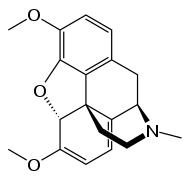

Morphinones and morphols

- 14-Cinnamoyloxycodeinone

- 14-Ethoxymetopon

- 14-Methoxymetopon

- 14-Phenylpropoxymetopon

- 3-Acetyloxymorphone

- 3,14-Diacetyloxymorphone

- 7-Spiroindanyloxymorphone

- 8,14-Dihydroxydihydromorphinone

- Acetylcodone

- Acetylmorphone

- Codeinone

- Codoxime

- Hydrocodone

- Hydromorphone

- Hydroxycodeine

- Metopon (=methyldihydromorphinone)

- Morphinone

- Morphol

- Oxycodone

- Oxymorphone

Structures

| Morphinones and morphols | ||||